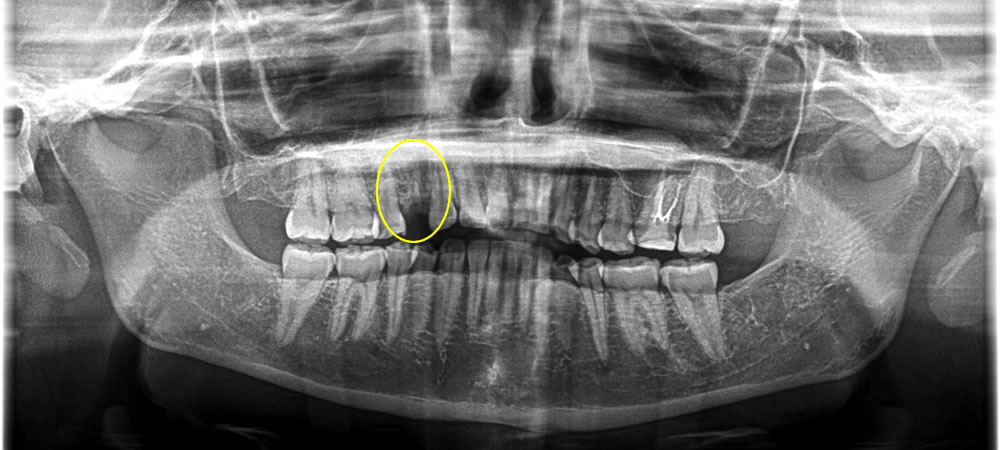

保存不可能な歯を抜歯後にインプラント治療を実施した症例

年齢

30代

性別

女性

症例を見る